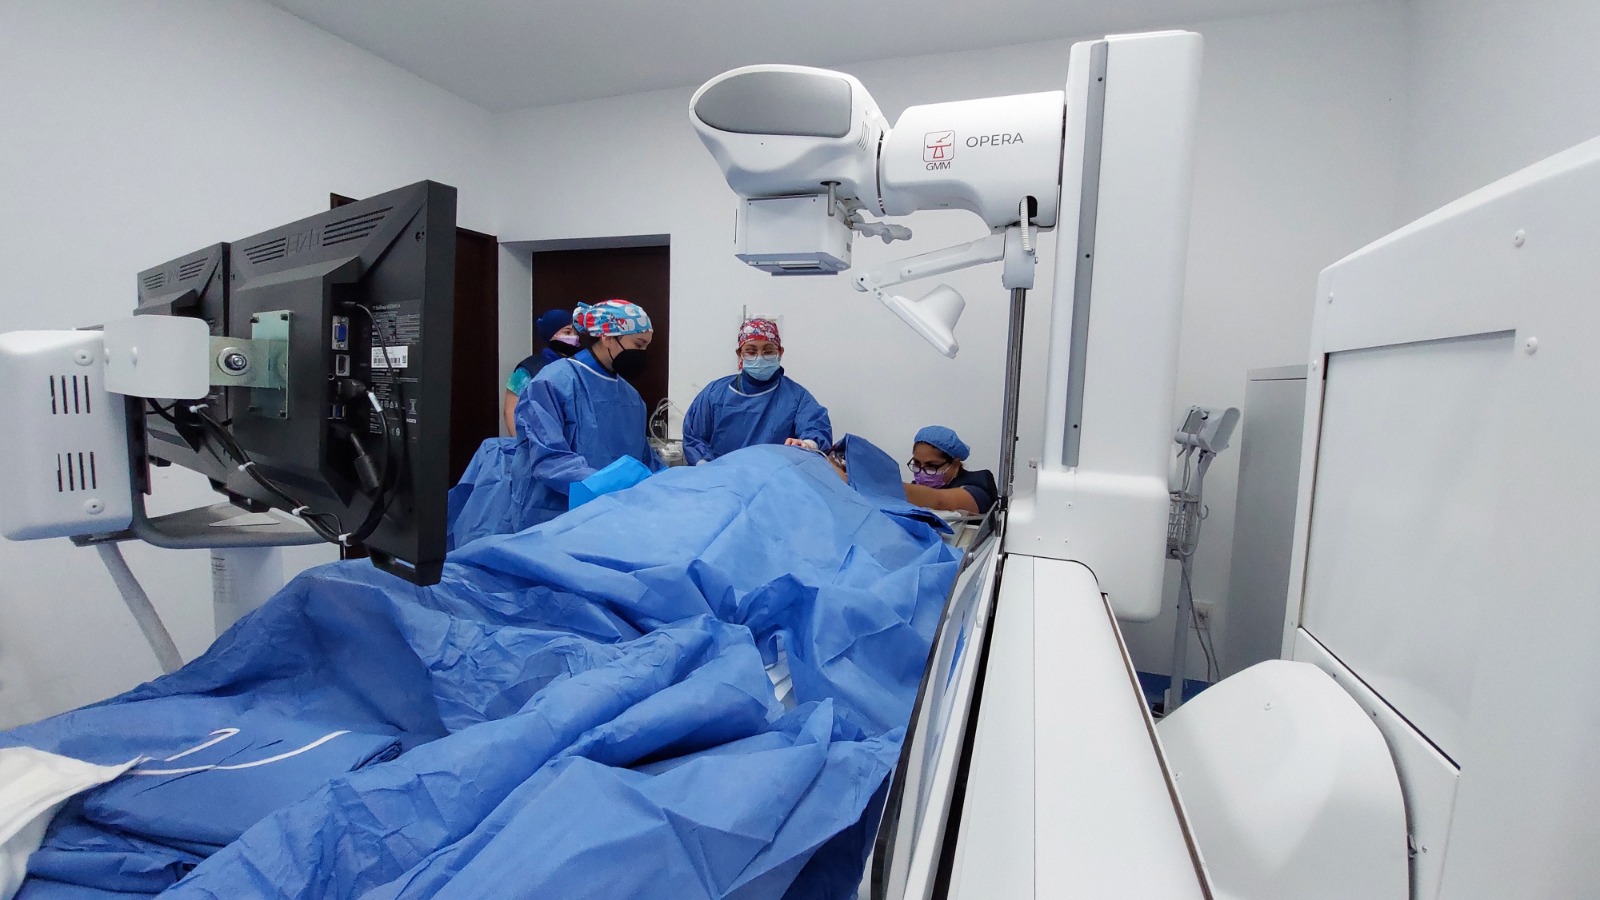

Tal es el caso de Iesus V, primer derechohabiente intervenido con el fluoroscopio a quien le colocaron un “Catéter Permacath”, el cual es utilizado para el tratamiento de hemodiálisis. A través de esta tecnología, la doctora Elena Solís Montero, del servicio de Angiología del HGR No. 12, colocó quirúrgicamente dicho catéter en el pecho del paciente.

“Poder ver en tiempo real la intervención del paciente, nos permite disminuir cualquier complicación y en este caso, como es un procedimiento endovascular, donde trabajamos las grandes venas del cuerpo, como la yugular o la cava superior, el tener esta tecnología, reducimos significativamente el riesgo de complicaciones en el paciente, quien podrá llevar a cabo su procedimiento de hemodiálisis, con una mayor durabilidad”, enfatizó la especialista.

Por su parte, la especialista en salud mencionó que el paciente a quien se le suministró anestesia local para realizar este procedimiento de mínima invasión aseguró que se sintió confiado por la experiencia de los médicos a quienes agradeció por su atención.

Agregó que para realizar estos procedimientos, se trabajó de manera coordinada entre el equipo de médicos especialistas en Angiología, Anestesiología, Imagenología y Rayos x.